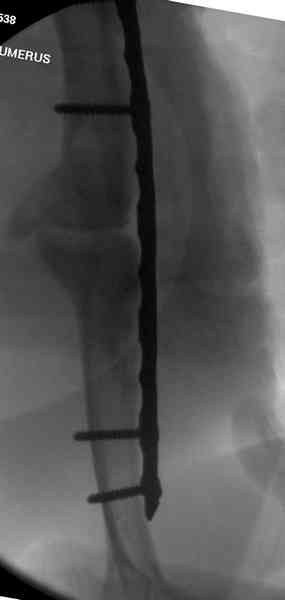

Помогите, пожалуйста, определиться с тактикой!Поступил больной с ложным суставом плечевой кости... Перелом был 2 года назад. Лечился в аппарате 8 месяцев, консолидации не произошло. В феврале 2007 выполнена костная аутопластика, фиксация пластиной (на базе одной из ИК). Сейчас сохраняется ложный сустав, плечо укорочено на 3 см, контрактура обоих смежных суставов, атрофия мышц плеча и плечевого пояса справа. Явлений остеомиелита не отмечалось. Больной - осужденный, сидеть ему до 2012 года.

Уважаемая Татьяна,

Как видно из выступлений коллег, способы фиксации

ложного сустава плеча могут быть различными, кто-то предпочитает аппаратом Илизарова (Соломин), пластинами (Волна) или интрамедуллярным гвоздем (Челноков).

Когда разбирался случай на сайте, и у нас была больная с похожей патологией, ложный сустав после поперечного перелома, леченного год назад где-то и кем-то в другом месте.

Мы не стали делать провокационный метод, который

предложил Корнеев для лечения - применение анаболических стероидов - ретаболила, из-за его бессмысленности, также не согласились с его теорией, что любая операция заблокирует суставы, а наоборот, провели жесткую фиксацию пластиной для раннего восстановления.

Первичную пластину убрали недели 6 назад из переднего оригинального доступа, и из-за подозрительности тканей вокруг пластины, решили провести реконструкцию поэтапно.

После промывки и дебридмента для уверенности уложили антибиотический цемент. Культура из раны в последующем была отрицательная.

Хотя сам не стороннник применения более массивных

имплантов для плеча, но для этого случая сделали

исключение. На снимке 4А диаметр мягких ткани около 20 см, при весе больной более 135 кг, и также выступление Андрея Волны подстегнуло к применению более массивной 4.5 мм локинг пластины.